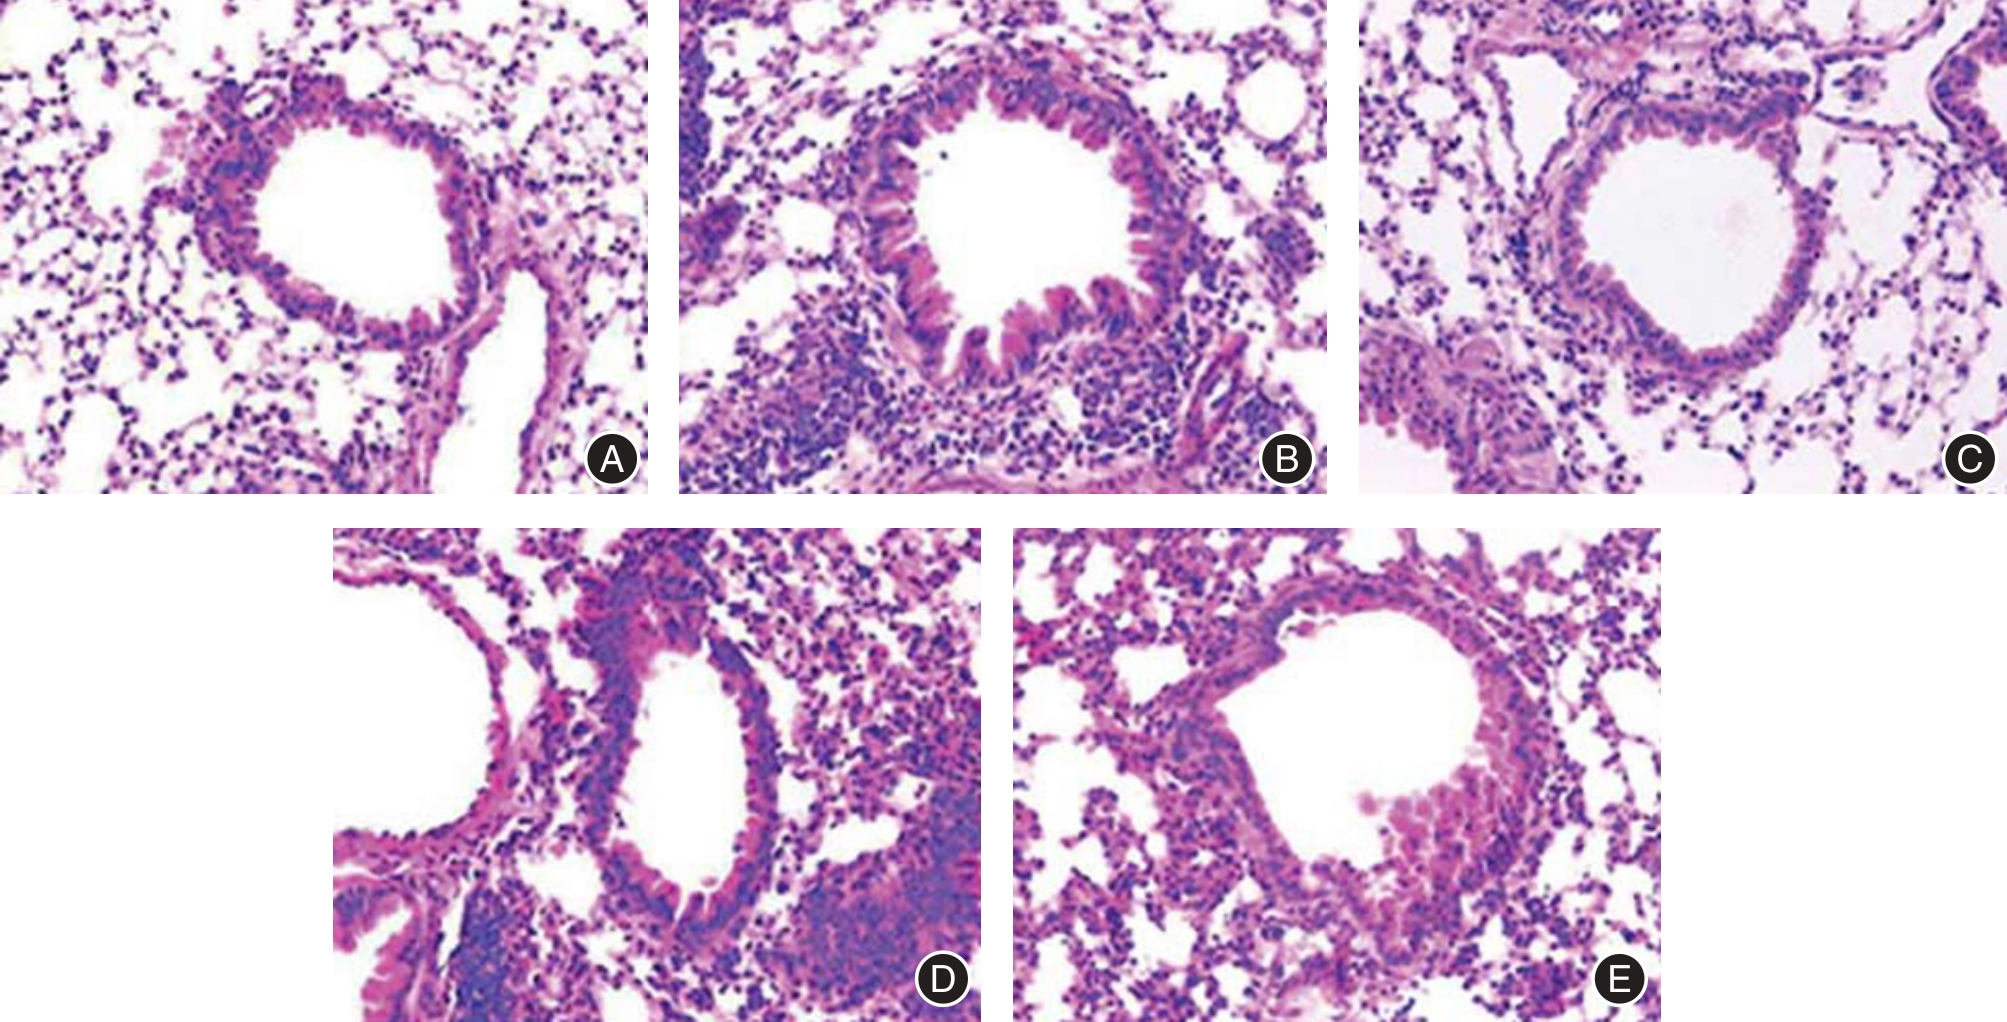

Objective To investigate the impact of Atractylodin on lung tissue damage in young asthmatic rats by regulating the CXC chemokine ligand 12 (CXCL12)/CXC chemokine receptor 4 (CXCR4) signaling pathway. Methods Twelve young SD rats were randomly selected from 60 rats as the control group (CON group), while the remaining 48 rats were used to construct asthma models using ovalbumin (OVA). Successfully modeled asthma rats were randomly separated into Model group, Atractylodin group (50 mg/kg Atractylodin), and CXCL-12 group (5 μg/kg recombinant CXCL-12 protein) and Atractylodin+CXCL-12 group (50 mg/kg Atractylodin+5 μg/kg recombinant CXCL-12 protein), with 12 in each group, continuously administered for 14 days. The CON and Model groups were given equal amounts of physiological saline. The percentages of neutrophils and eosinophils in bronchoalveolar lavage fluid (BALF) were detected. ELISA method was applied to detect cytokine levels in serum and BALF fluid; HE staining was applied to detect pathological changes in lung tissue; Western blot was applied to detect the levels of CXCL12/CXCR4 pathway related proteins. Results Compared with the CON group, the pathological score of lung tissue, percentage of neutrophils, percentage of eosinophils, the levels of IL-17, IL-4, IL-5, IL-13, IgE, OVA sIgE, and the protein levels of CXCL12 and CXCR4 in Model group were obviously increased (P < 0.05); compared with the Model group, the pathological score of lung tissue, percentage of neutrophils, percentage of eosinophils, the levels of IL-17, IL-4, IL-5, IL-13, IgE, OVA sIgE, and the protein levels of CXCL12 and CXCR4 in the Atractylodin group were obviously reduced (P < 0.05), the results in the CXCL-12 group were opposite to those in the Atractylodes group; CXCL-12 eliminated the improvement effect of atractylodes on asthma rats. Conclusion Atractylodin may improve lung tissue damage in asthmatic rats by down-regulating the CXCL12/CXCR4 signaling pathway.